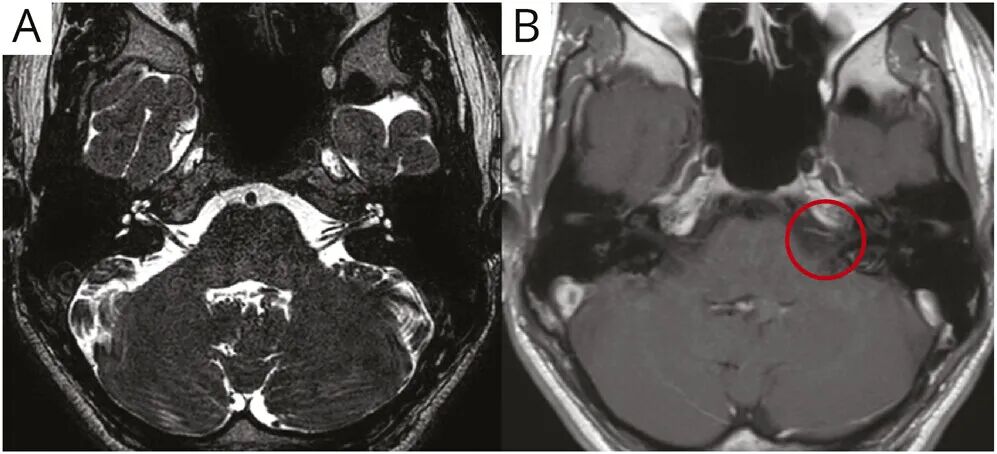

本例中,病毒感染前驱症状的存在以及缺乏中枢神经系统体征支持前庭神经炎的诊断。脑部增强

图1 脑部磁共振成像(A:未注射钆对比剂的T2加权像显示正常解剖结构 B:注射钆对比剂后的T1加权像显示左侧前庭耳蜗神经强化,红圈标示)